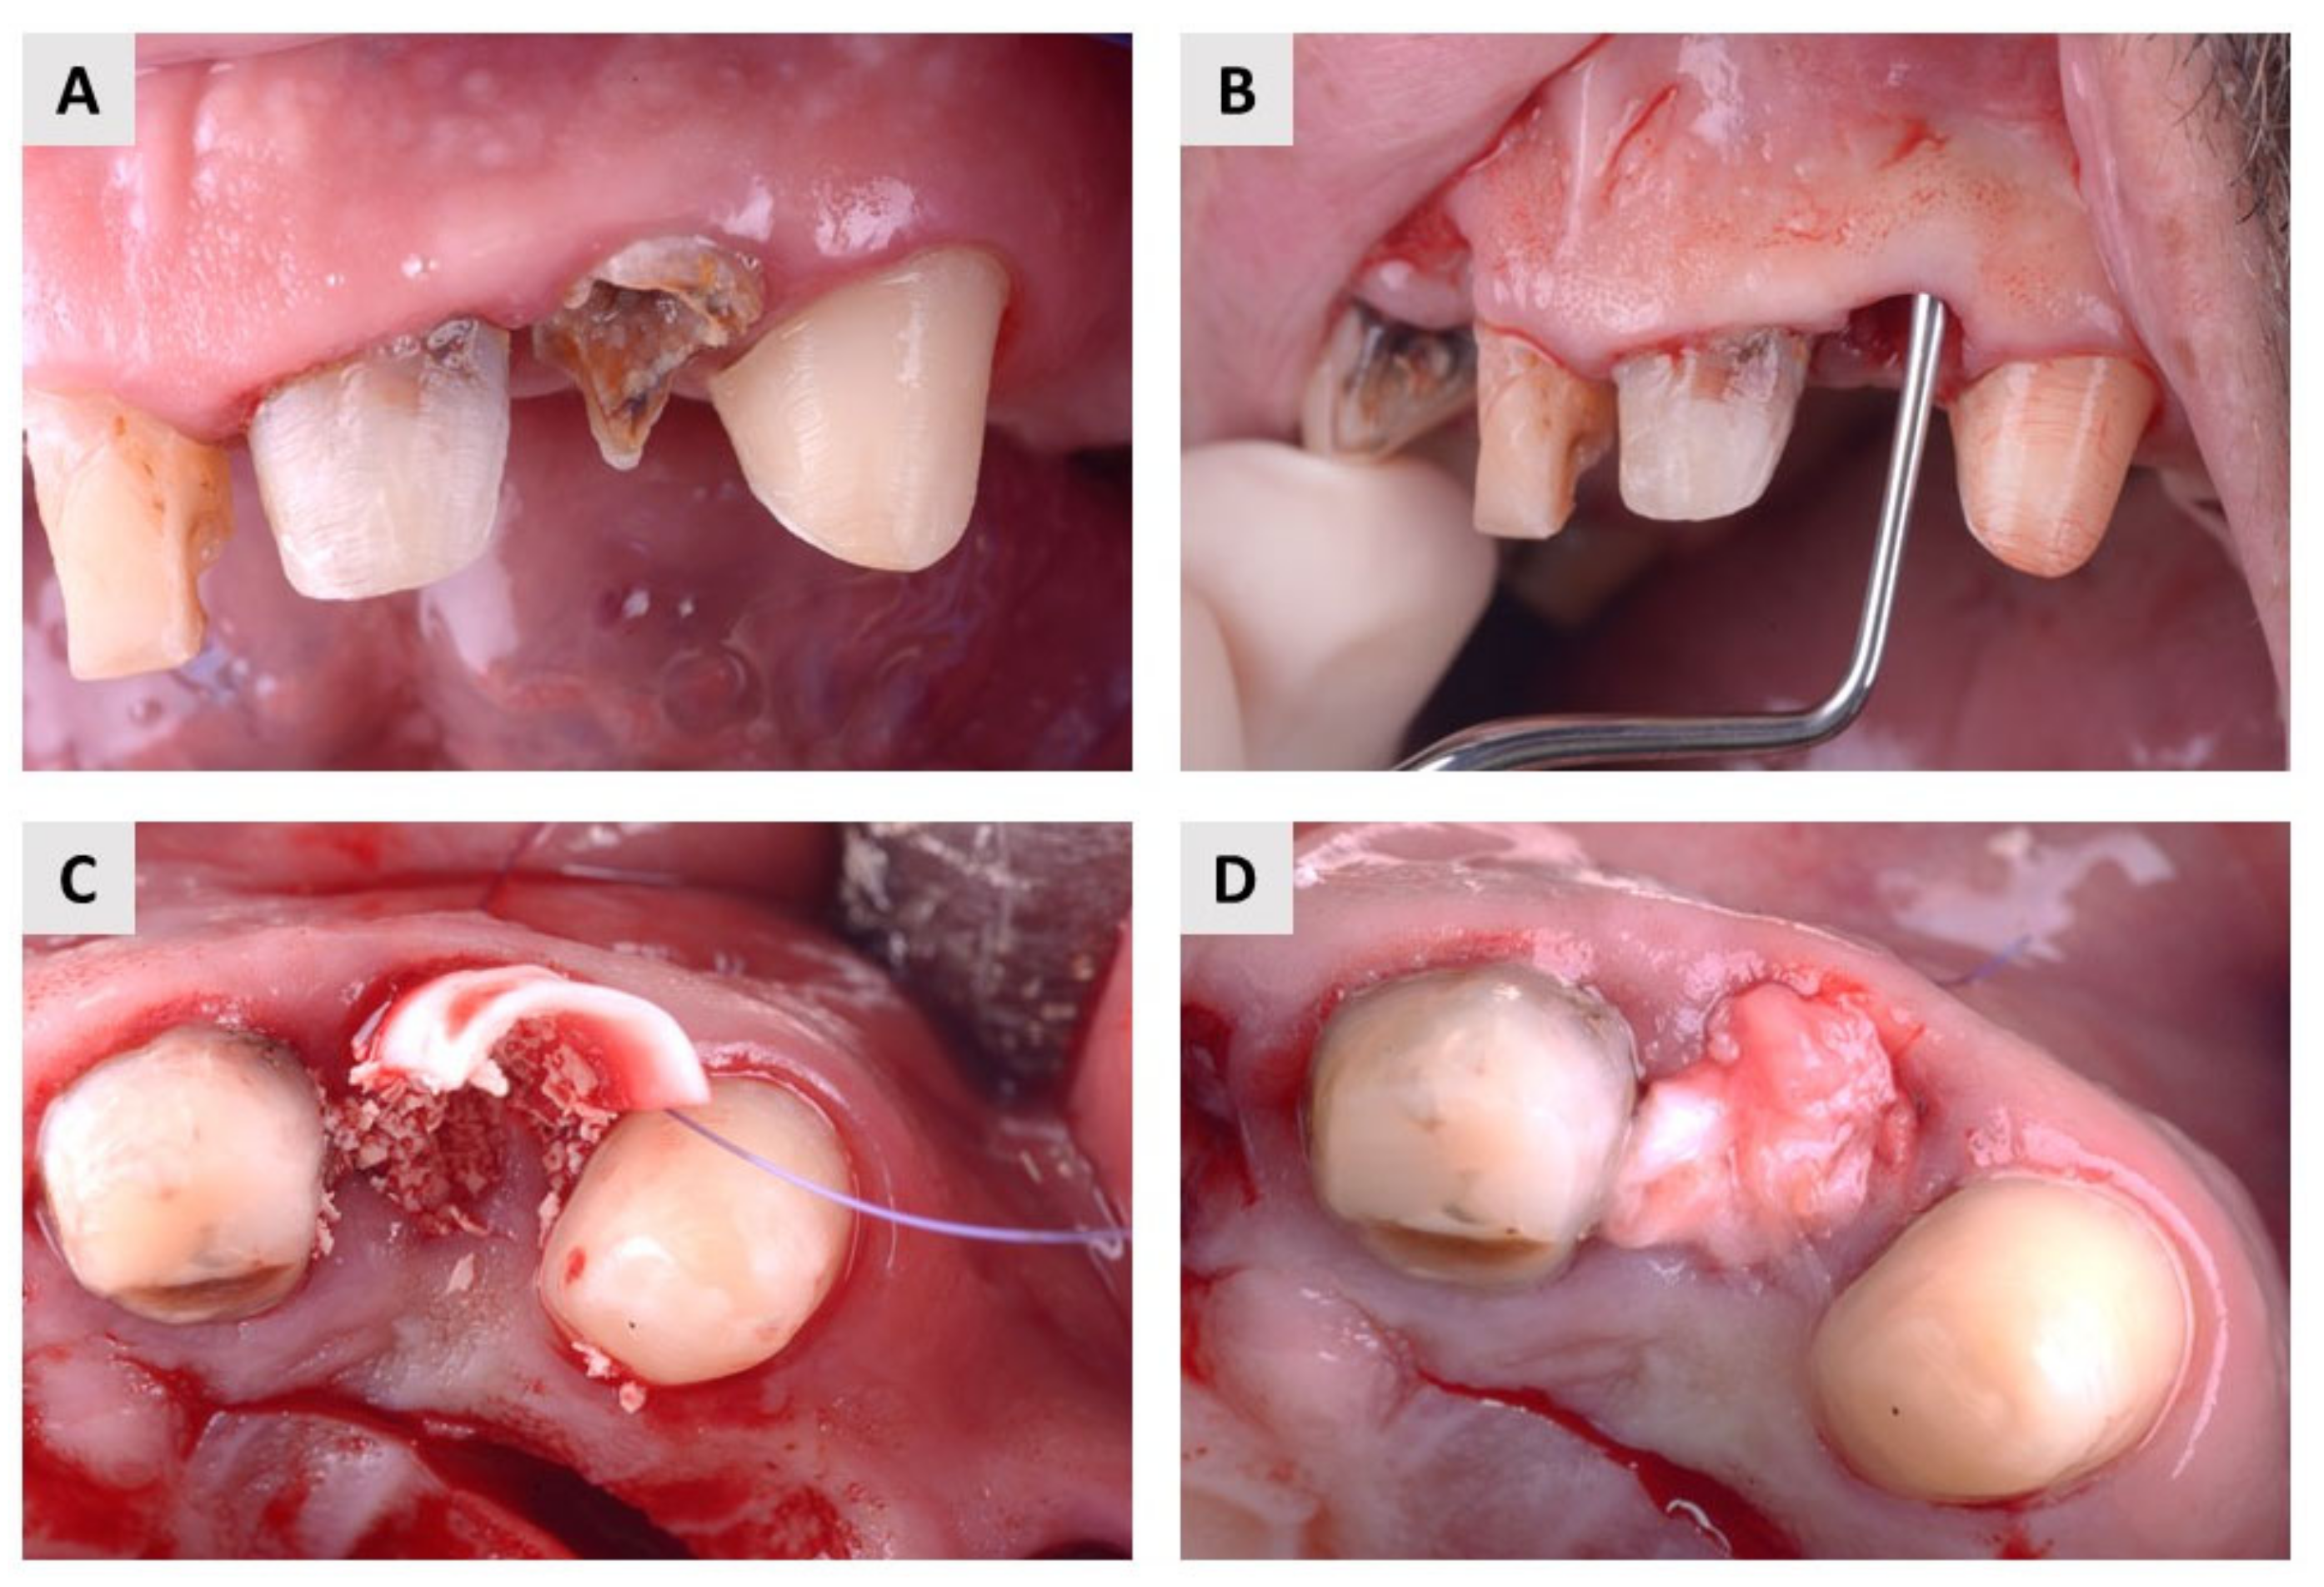

4.2. Surgical Procedure and Postoperative Follow-Up